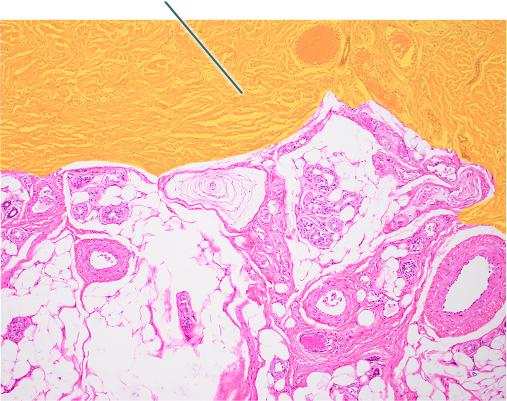

Which type of tissue is the highlighted region composed of?

stratum corneum

stratified squamous epithelium, keratinized

stratum spinosum

dermis

stratified squamous epithelium, keratinized

Which layer of the skin is highlighted?

papillary layer of dermis

reticular layer of dermis

hypodermis

epidermis

papillary layer of dermis

Which region of the skin is highlighted?

hypodermis

reticular layer of dermis

epidermis

papillary layer of dermis

Which structures would you expect to find in the highlighted

layer?

adipose tissue only

free nerve endings only

blood vessels, free nerve ending, and receptor cells

blood vessels only

blood vessels, free nerve ending, and receptor cells

Which layer is highlighted?

papillary layer of dermis

hypodermis

reticular layer of dermis

epidermis

hypodermis

Reticular layer of the dermis

C

Hypodermis

D

Epidermis

A